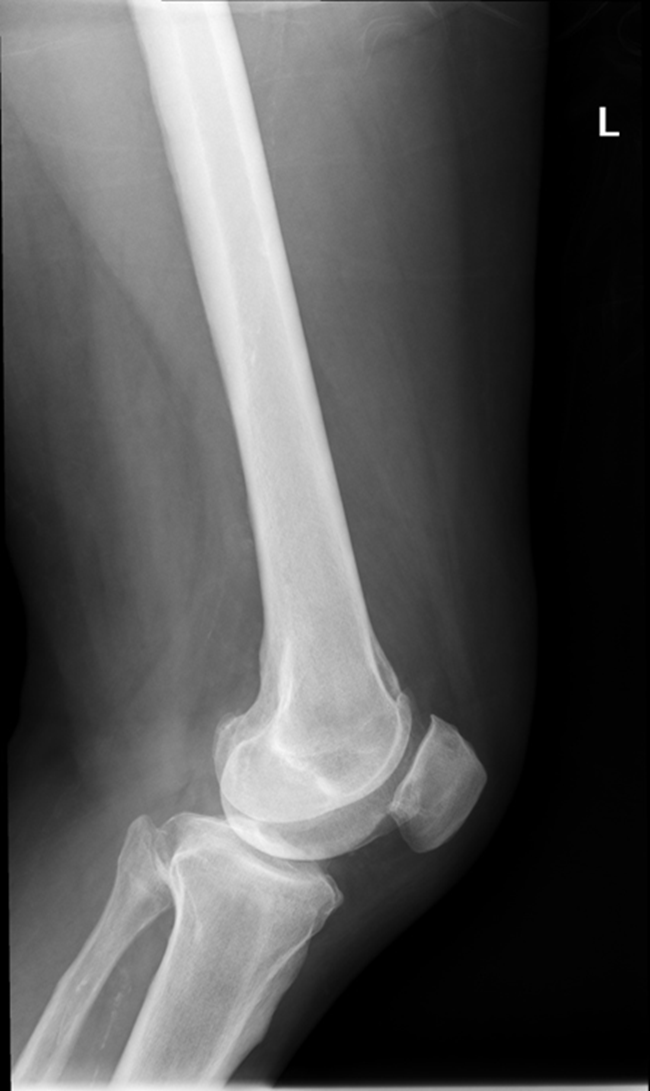

AP Femur

•Evidence of proper collimation and the presence of a side marker placed clear of the anatomy of interest

•Most of the femur and the joint nearest to the pathologic condition or site of injury (a second projection of the other joint is recommended)

•Femoral neck not foreshortened on the proximal femur

•Lesser trochanter not seen beyond the medial border of the femur or only a very small portion seen on the proximal femur

•No knee rotation on the distal femur

•Gonad shielding when indicated, but without the shield not covering proximal femur

•Any orthopedic appliance in its entirety

•Bony trabecular detail and surrounding soft tissues

Travsverse displaced subtrochanteric fractrue proximal right femur